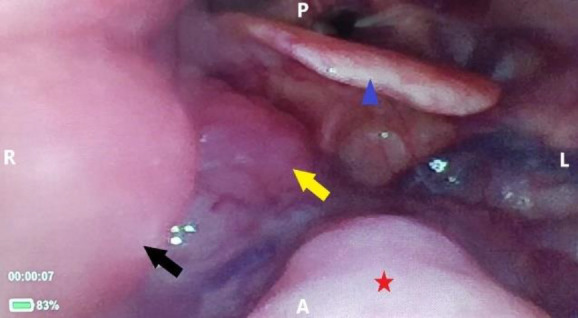

Introduction: Tuberculosis (TB) is an important contagious disease and a major public health problem globally. It may manifest as pulmonary TB or primary or secondary extrapulmonary TB. Primary oropharyngeal TB is very rare and may mimic presentation of oropharyngeal malignancy especially in the negative initial TB workup.

Case report: We would like to highlight a case of an elderly man presented with ipsilateral oropharyngeal mass and cervical lymph node (LN) enlargement, mimicking oropharyngeal malignancy with regional LN metastasis.